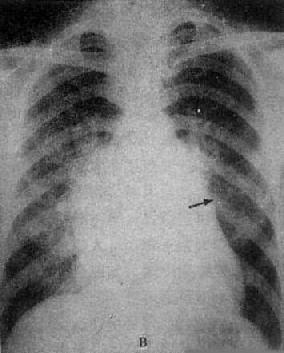

X线表现(图3-2-16),二尖瓣回流较轻,心代偿功能良好时,心大小和形状无明显改变,仅见左心房和左心室轻度增大,当二尖瓣回流在中度以上,心肌代偿功能较差时,则左心房明显增大,在心室也增大,透视下可见左心室收缩时因瓣膜关闭不全而左心房有强烈的搏动。肺有瘀血,右心室亦可增大。主动脉球正常或略小。

图3-2-16 二尖瓣关闭不全并狭窄

心增大呈二尖瓣型,右心室增大,肺动脉

段突出,左心耳增大,有肺瘀血